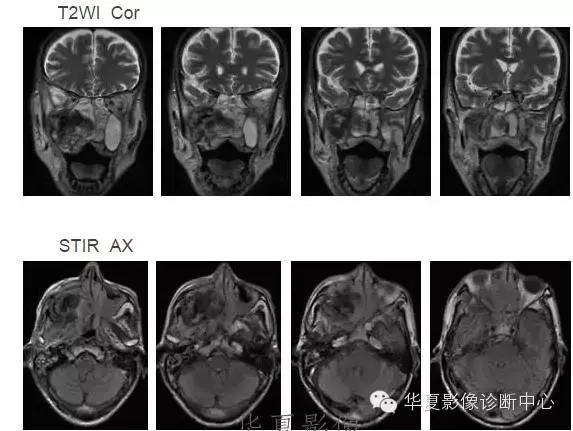

中枢神经系统内原发性黑色素瘤少见, 因脑和脊髓的软脑( 脊) 膜及蛛网膜上含有黑色素细胞, 黑色素可发生于软脑( 脊) 膜的任何部位,故其发生部位常位于脑( 脊髓) 表面, 沿软脑膜生长; 而继发性黑色素瘤同一般转移性肿瘤, 常位于灰白质交界区。

影像表现:常表现为短 T1 高信号, 短T2WI 低信号,又因为黑色素瘤是富血管性肿瘤, 增强扫描常表现为明显强化。

★但少数肿瘤也不具备上述典型信号特征,主要原因是肿瘤内黑色素量多少影响。只有当黑色素瘤中黑色素细胞超过一定含量( ﹥ 10% ) 时, 才会出现黑色素瘤的典型MRI表现; 不典型的黑色素瘤因其黑色素含量较少,不足以缩短T1、T2弛豫时间,而表现为长T1低信号、长T2高信号。

依据黑色素瘤的不同 MRI 影像表现将其分为 4 种类型: ( 1) 黑色素型。该黑色素瘤因含有丰富的黑色素颗粒, MRI表现较典型,即短 T1 高信号,短 T2 低信号。( 2) 无黑色素型。因该类黑色素瘤不含黑色素颗粒或含量较低,MRI 表现为长 T1 低信号,长 T2 高信号; ( 3) 混合型。黑色素型和非黑色素型两者的混合; ( 4) 出血型。表现为血肿不同时期的信号特征, 该黑色素瘤 MRI增强扫描表现为不均匀环状或弥漫性强化